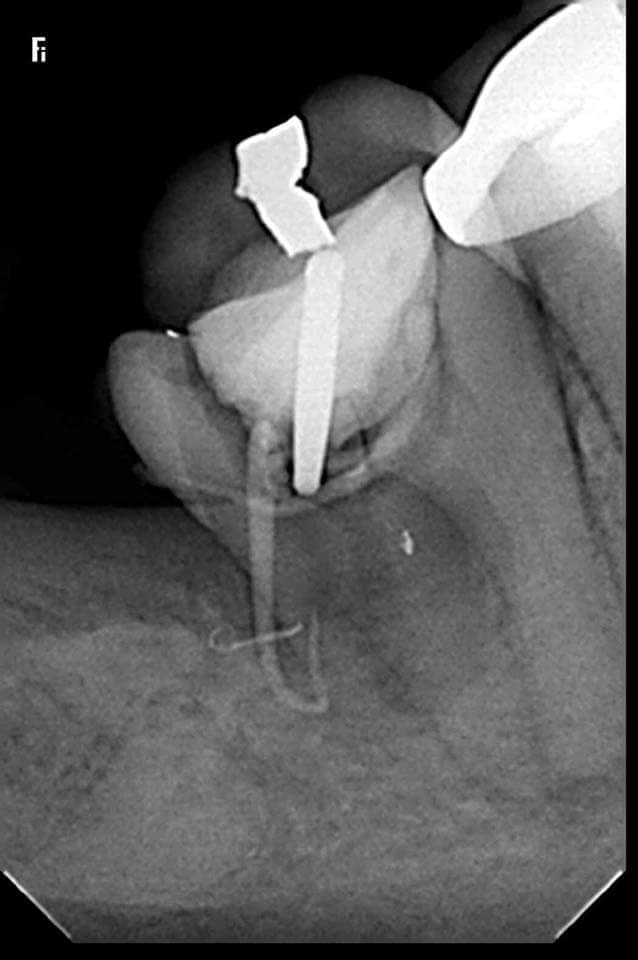

Et tu fais la radio en court de prepa... pour le gentil cdc.

Un cdc de la secu. Tous les ans 30 cas aleatoires oc endo pour un "petit" praticien radio post op (interpretation par une ia).